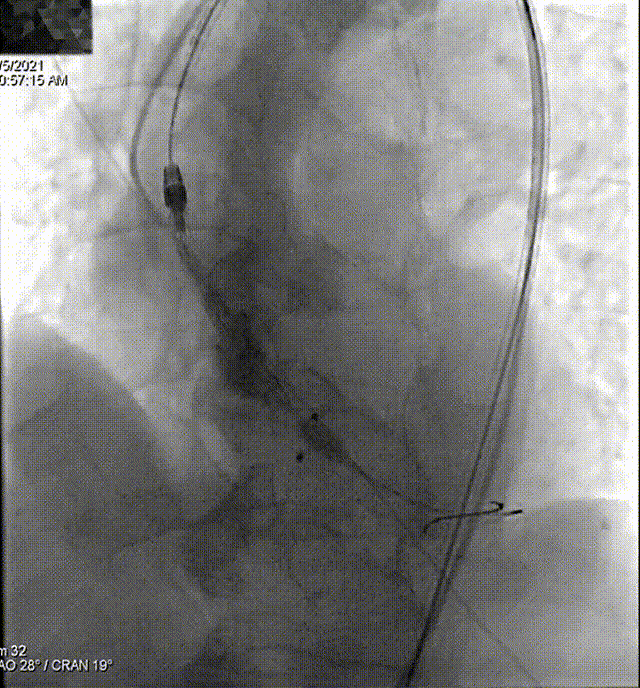

主动脉根部造影

Lunderquist导丝垮瓣

快速起搏下球囊预扩

瓣膜过弓、跨瓣

冒烟确认到达预期位置

160次/min快速起搏下完成瓣膜释放,植入24 mm VitaFlow瓣膜

180次/min快速起搏下22 mm球囊行后扩处理

最终释放效果

术后,患者跨瓣压差由术前的57mmHg降至术后1mmHg,仅少量瓣周漏。